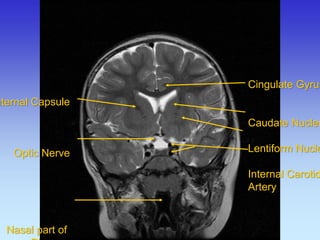

Cingulate Gyrus

Caudate Nucleus

Lentiform Nucleus

Internal Carotid

Artery

Longitudinal Fissure Lateral Sulcus Superior Sagittal

Sinus

Genu of Corpus

Callosum

Temporal Lobe